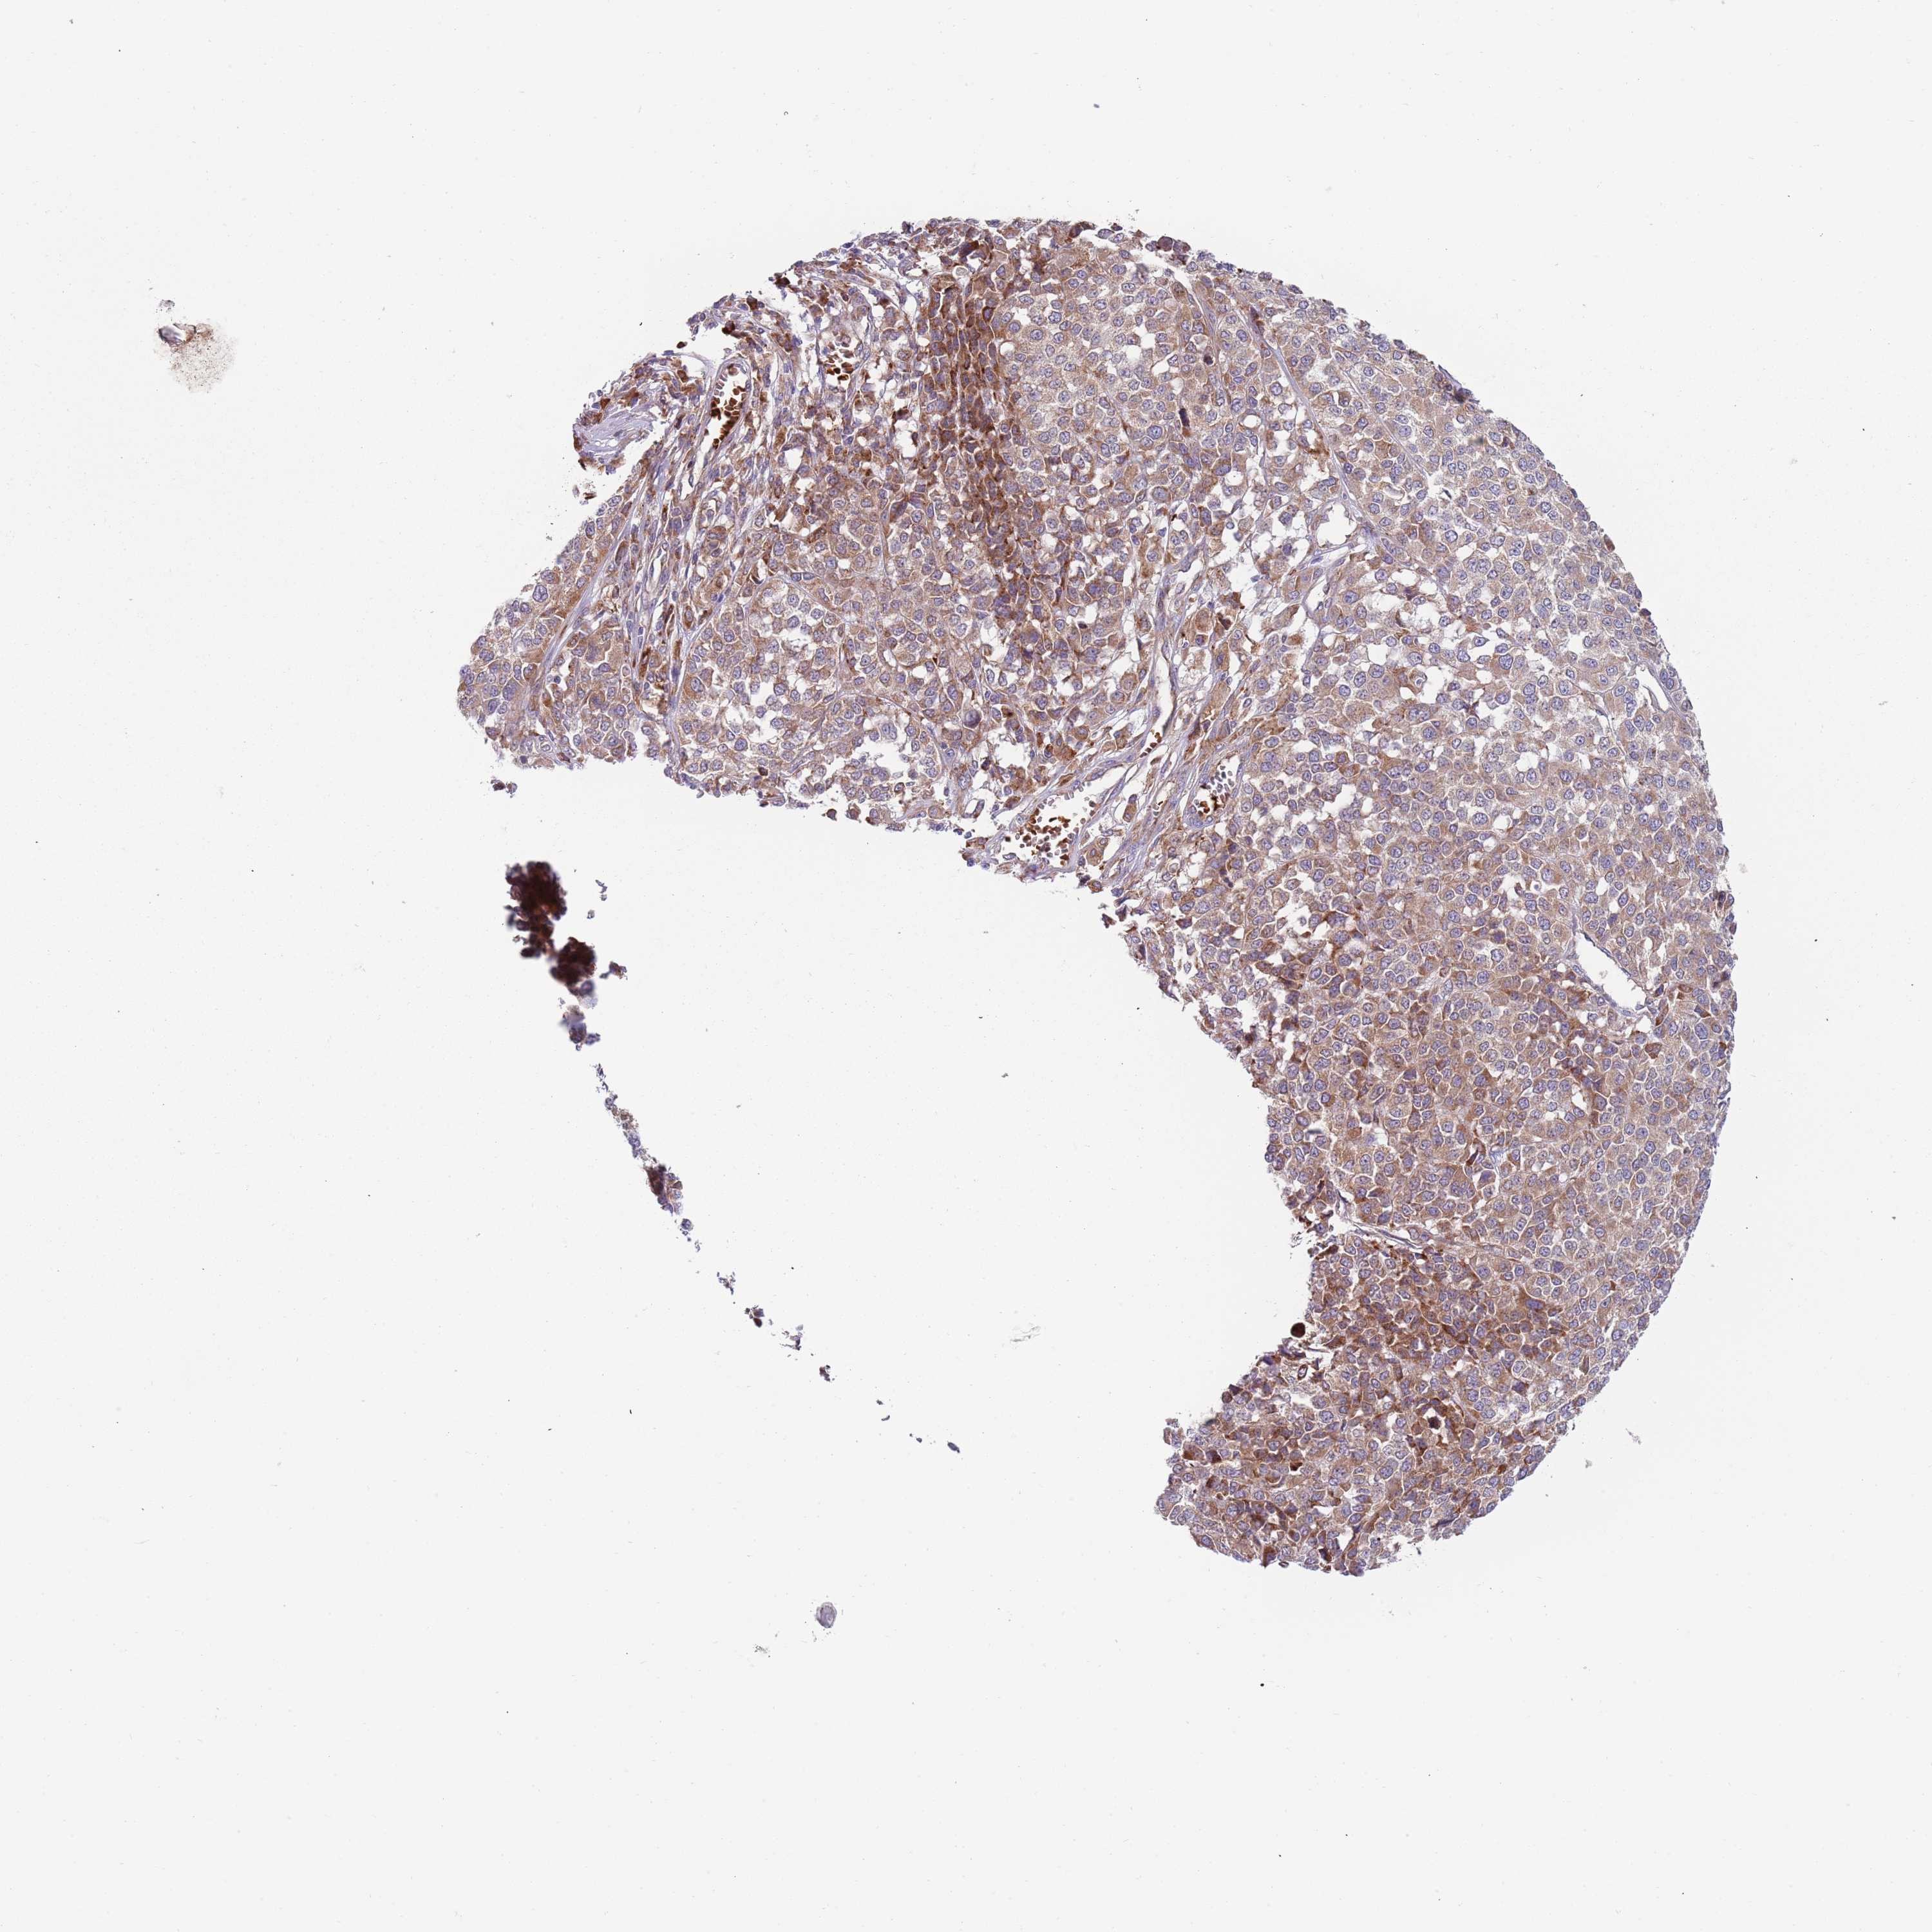

MELANOMA - Protein expressioni

A mouse-over function shows sample information and annotation data. Click on an image to view it in a full screen mode. Samples can be filtered based on level of antibody staining by selecting one or several of the following categories: high, medium, low and not detected. The assay and annotation is described here.

Note that samples used for immunohistochemistry by the Human Protein Atlas do not correspond to samples in the TCGA dataset.

Antibody stainingi

Antibody staining in the annotated cell types in the current human tissue is reported as not detected, low, medium, or high, based on conventional immunohistochemistry profiling in selected tissues. This score is based on the combination of the staining intensity and fraction of stained cells.

Each image is clickable and will lead to virtual microscopy that enables deeper exploration of all samples and also displays staining intensity scores, fraction scores and subcellular localization as well as patient and tissue information for each sample.

Antibody HPA040401

Antibody HPA043921

Staining

High

Medium

Low

Not detected

Intensity

Strong

Moderate

Weak

Negative

Quantity

>75%

75%-25%

<25%

None

Location

Nuclear

Cytoplasmic/membranous

Cytoplasmic/membranous,nuclear

Malignant melanoma, NOS

Malignant melanoma, Metastatic site